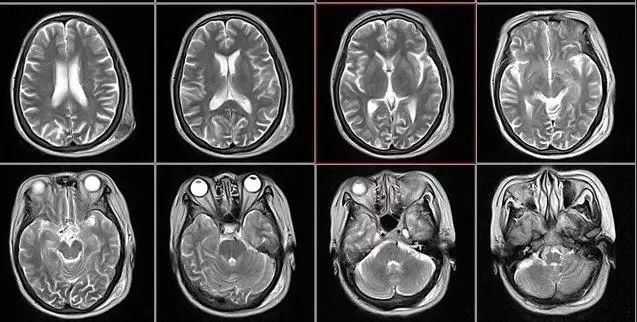

核磁共振:摇一摇再看

核磁共振机使用较强大的磁场,使人体中所有水分子磁场的磁力线方向一致,这时磁共振机的磁场突然消失,身体中水分子的磁力线方向,突然恢复到原来随意排列的状态。简单说就相当于用手摇一摇,让水分子振动起来,再平静下来,感受一下里面的振动。所以,核磁共振(MRI)也被戏说为是摇摇看的检查。